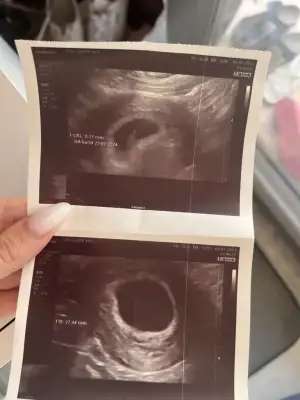

kalbini gördük pıt pıt atıyor pirinçten büyük boyu

kalbini gördük pıt pıt atıyor pirinçten büyük boyu  her şey yolundaymış şükür

her şey yolundaymış şükür